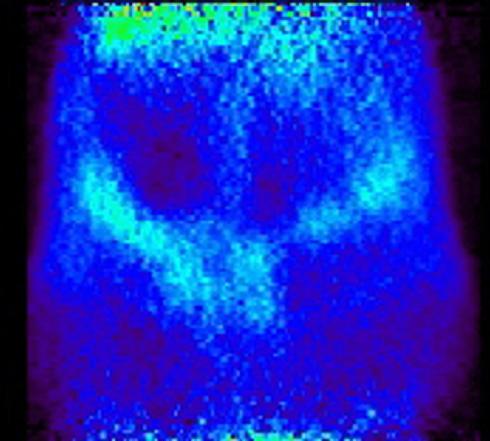

Several inhaled drug formulations were studied by radiolabeling the active ingredient (several different steriods) with C-11 or F-18, formulating that ingredient as the dosage form (different MDI, DPI, and nebulizer formulations), and performing quantitative PET studies of the regional biodistribution and kinetics.

Click on images to see additional examples, larger versions, and videos.